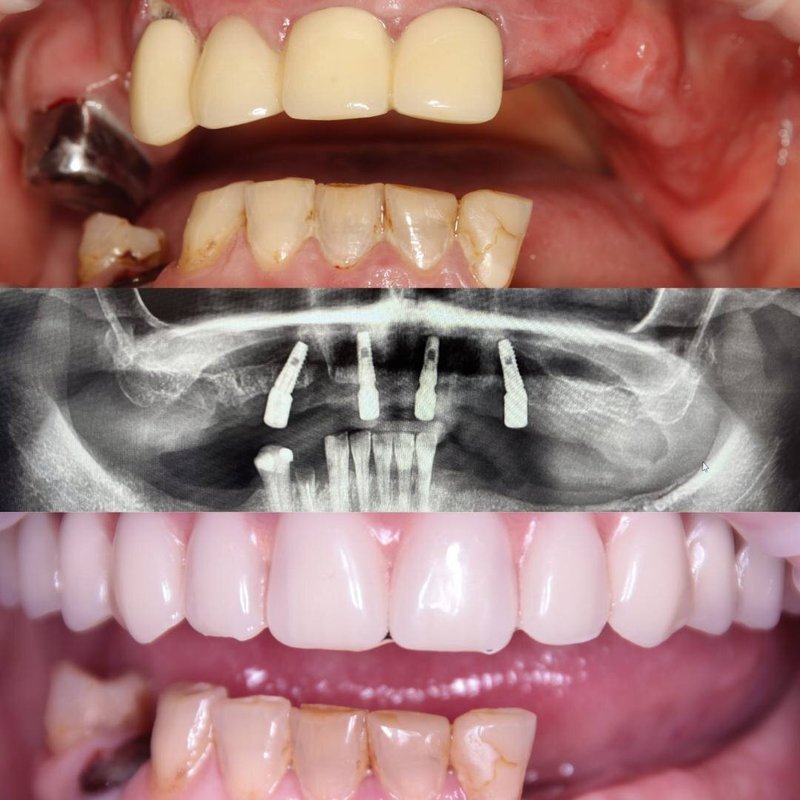

Фотогалерея

Если вы собираетесь добиться сияющей улыбки, то работу над ней лучше доверить экспертам. В стоматологической клинике Династия Н имеется специализированное оборудование для того, чтобы ваши зубы снова стали белоснежными. В нашей стоматологии оказывают услуги лечения кариеса, удаления зубов, компьютерной томографии, отбеливания, исправления прикуса, рентгенологической диагностики, изготовления имплантов, а также установки металлокерамики, брекетов, имплантов, виниров. С нами ваша улыбка будет яркой, а зубы крепкими!

Виталия Владимировна – опытный, талантливый и квалифицированный стоматолог-хирург и имплантолог. За её плечами около 1000 установленных имплантатов, более 500 проведенных операций. Стремится предоставлять своим пациентам самый высокий уровень медицинского сервиса и индивидуальное лечение. Специализируется на выполнении быстрых и аккуратных удалений зубов и безболезненной установке имплантов. Заботится не только о функциональной составляющей лечения, но и об эстетической. Ее талант, высокий уровень профессионализма, опыт, внимание к деталям и индивидуальный подход признаются как пациентами, так и профессиональным сообществом. Как услуги оказывает врач Изучает каждый клинический случай совместно с коллегами и зуботехнической лабораторией, что позволяет объединить знания и многолетний опыт квалифицированных специалистов. Разрабатывает оптимальные планы лечения. Выполняет широкий спектр хирургических процедур, включая имплантацию, сложные случаи удаления зубов, наращивание костной ткани, синус-лифтинг. Проводит удаления различных новообразований в полости рта, таких как папилломы, фибромы и другие. Проводит мягкотканные пластики, пластики рецессии десны.